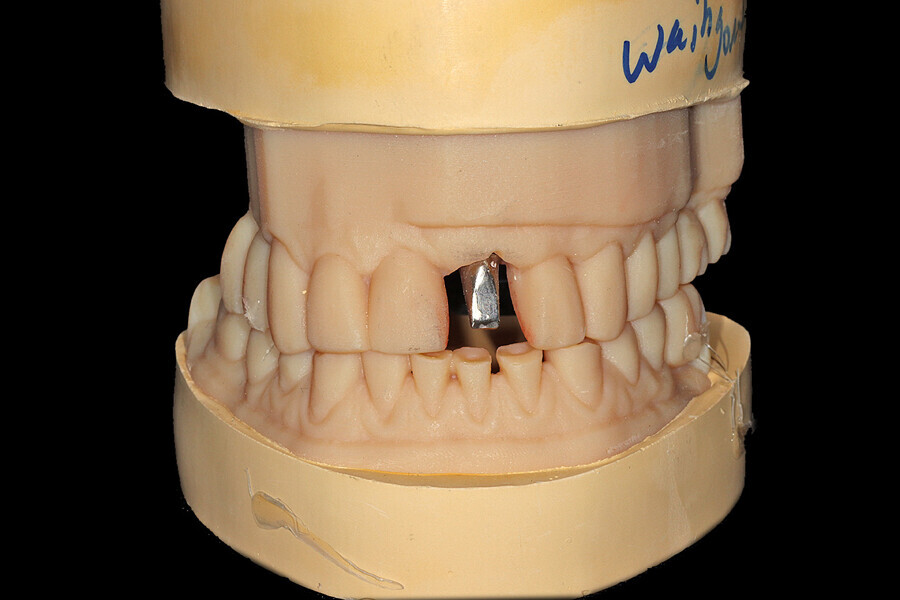

Fig. 25: Using an implant-specific SmartPeg, a baseline ISQ value of 76 confirmed sufficient initial stability to place an immediate restoration.

Fig. 26a: The prefabricated CAD/CAM abutment and transitional crown

Fig. 26b: A post-op periapical radiograph confirmed successful sub-crestal placement of

this platform-switched design.

Fig. 26c: The abutment in place.

Fig. 26d: The soft-tissue contours were excellent; no sutures were required for the transitional restoration.